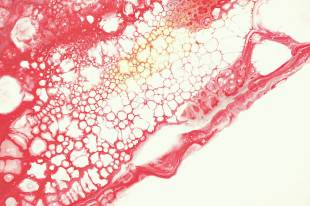

HDL 콜레스테롤 이란 혈관 속을 떠도는 지질 찌꺼기를 회수해 간으로 되돌려보내는 일종의 정화 장치로, 순환계 내부에서 환경미화원과 같은 역할을 수행하는 보호 인자로 설명됩니다. 이 물질은 저밀도 지질과 달리 동맥벽에 쌓이는 성질이 거의 없으며, 오히려 이미 축적된 지방 성분을 끌어안고 이동하는 역수송 경로를 활성화해 혈관 내강을 비교적 매끄럽게 유지하는 데 기여합니다.

이러한 작용은 죽상경화 진행을 늦추는 핵심 기전으로 간주되며, 심혈관 질환 위험도를 평가할 때 중요한 생화학적 지표로 활용됩니다. 혈액검사 수치 하나가 전신 혈류의 질서를 반영한다는 점에서 임상적 의미가 크다고 할 수 있습니다.

이 지질 단백은 간과 소장에서 합성된 이후 말초 조직을 순환하며 과잉 지방산과 콜레스테롤 에스터를 흡수하는 독특한 경로를 따릅니다. 이러한 생화학적 변환은 혈관 내 염증 반응을 완화하고 산화 스트레스를 낮추는 방향으로 작용합니다. 결국 이 지표는 단순한 지방 숫자가 아니라 대사 균형의 척도로 이해할 수 있습니다.

수치가 낮은 상태에서는 혈관 내벽에 지방 잔여물이 쌓이기 쉬운 환경이 조성됩니다. 이는 청소 기능이 약화된 도로에 먼지가 계속 쌓이는 상황과 유사하며, 장기적으로 혈류 흐름을 방해하는 요인이 됩니다. 초기에는 특별한 자각 증상이 없을 수 있으나, 내부적으로는 염증 반응이 서서히 진행됩니다. 이러한 변화는 조용히 진행된다는 점에서 위험성이 큽니다.